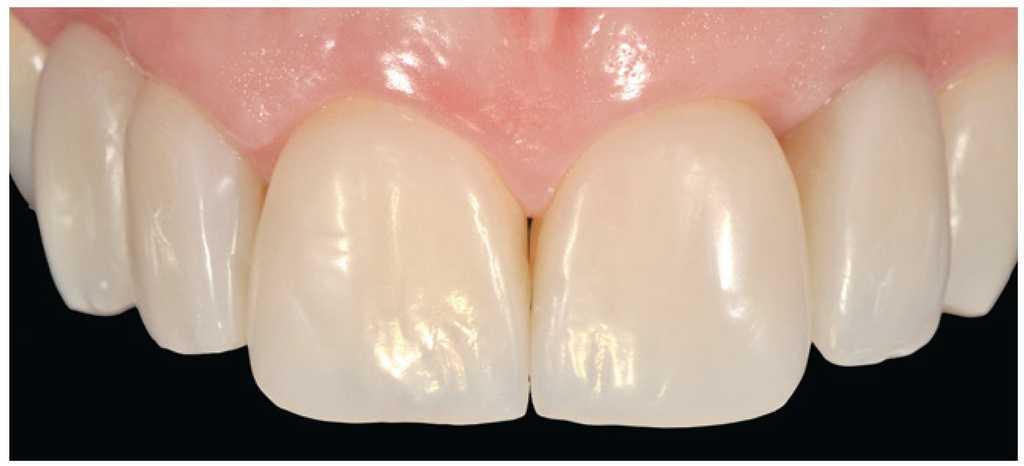

Figura 3 El caso terminado tras la reconstrucción con composite, realizada tras la cicatrización de los tejidos gingivales.